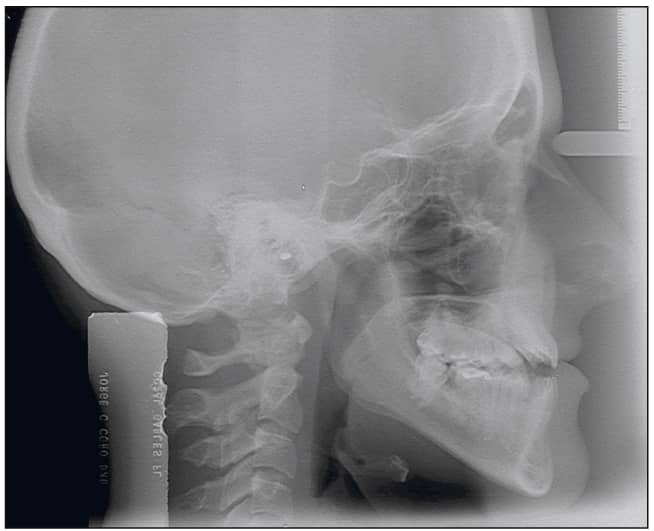

The patient, a 26-year-old female, presented with a chief complaint that she did not like her smile and was unable to bite with her front teeth. She presented with a concave profile due to an apparent midface deficiency and mandibular prognathism. She had a Class III anterior open bite malocclusion, confirmed by the cephalometric analysis (Figures 2 to 4).